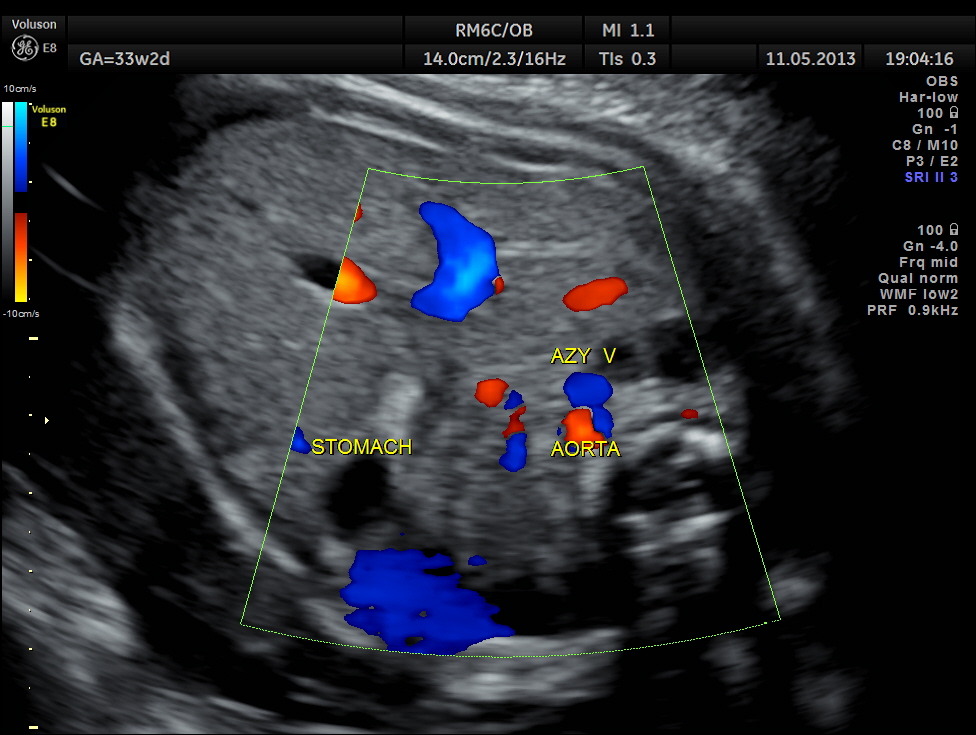

The first picture would confirm the left atrial isomerism – aorta and azygos vein seen side by side .